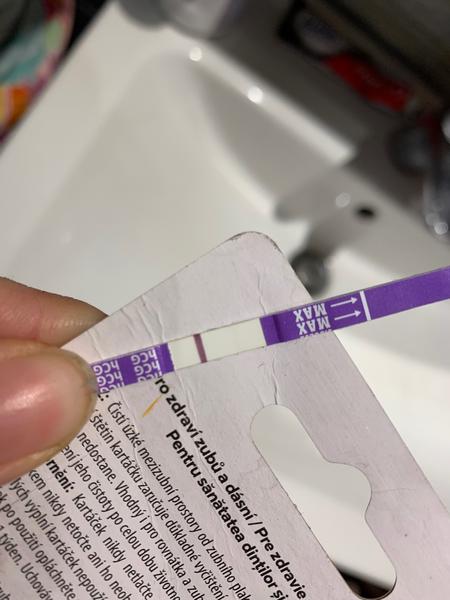

Zdravím, prosím o vaši nynější zkušenost s testy Dr.Max. Během let se jejich kvalita měnila několikrát. Jsem nyní 34.dc tj cca 4dny meškání os obvyklé MS. V tomto cyklu jsem 17. a 18.cd špinila, ale kdy byla ovulace nevím. Dnes jsem si udělala test a po celý limit byl bílý. Pak cca po 1,5hod jsem ho šla vyhodit a je na něm toto. Máte zkušenost s ryskami u tohoto testu po limitu? Děkuji

Děkuji, také jsem právě brala test jako jasně negativní, když do 10min nic neukázal. Ale až po takové době jsem objevila ve skutečnosti hezky viditelnou čárku (do růžova je, zkusím ještě lépe vyfotit). Zkusím ještě další test třeba zítra nebo pozítří..🥴

@vnikan tyto testy mi většinou dělaly rysky, co se objevily po 10 minutách, takže jsem to nebrala. Ale když tam opravdu čárka byla, objevila se hned. Sice hodně slaboučká, ale hned. Ovšem nešla takhle pěkně vyfotit, jako tvoje. Takže si vlastně neporadím 😅 ale budu držet palce, ať to dopadne 😊

@vnikan na začátku se může objevit čárka i po limitu ,prostě je to pozitivní,zkuste obden další tt,čárka musí sílit